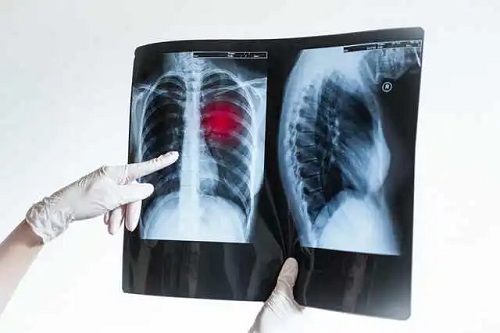

Pneumonia este o boală pulmonară infecțioasă foarte frecventă. Constă în inflamația țesutului pulmonar, însoțită de o creștere și condensare a secrețiilor în spațiile alveolare. Acestea sunt sacii pulmonari în care are loc schimbul de gaze: oxigen și CO2.

Acest lucru provoacă o schimbare a funcțiilor pulmonare, ceea ce poate pune sănătatea în pericol. Deși majoritatea cazurilor se rezolvă fără complicații, unii pacienți rămân cu sechele după pneumonie, care le afectează calitatea vieții.